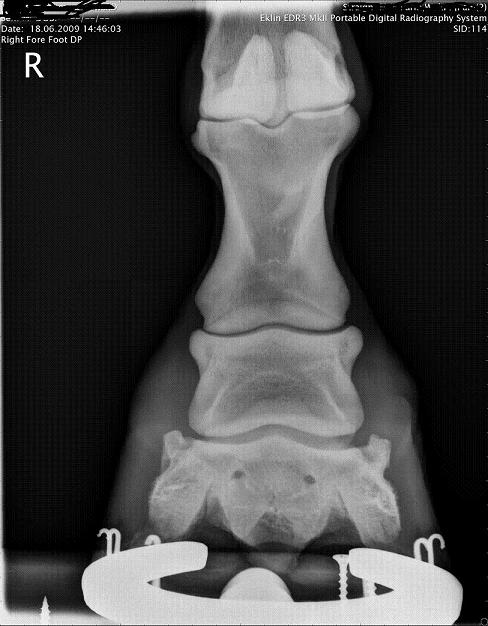

RF DP

"changes on ventral border of navicular bone within normal limits. slight erosion of toes right fore..small OSC chip left hind."

"foot balance synDrOme producing pedal bone compression"

1) I believe your veterinarian is saying poor foot balance has put extra stress on the coffin bone as demonstrated by the changes in the tip he describes. He believes that balancing the foot and relieving break over and reduced exercise the horse in time will come sound for full work again. I have to ask did he also do a posterior digital block prior to the ab. ses. block?